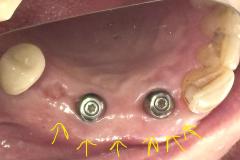

Implants placed using a digitally planned stackable surgical guide following alveolectomy, ensuring ideal positioning and a stable foundation for full-arch restoration.